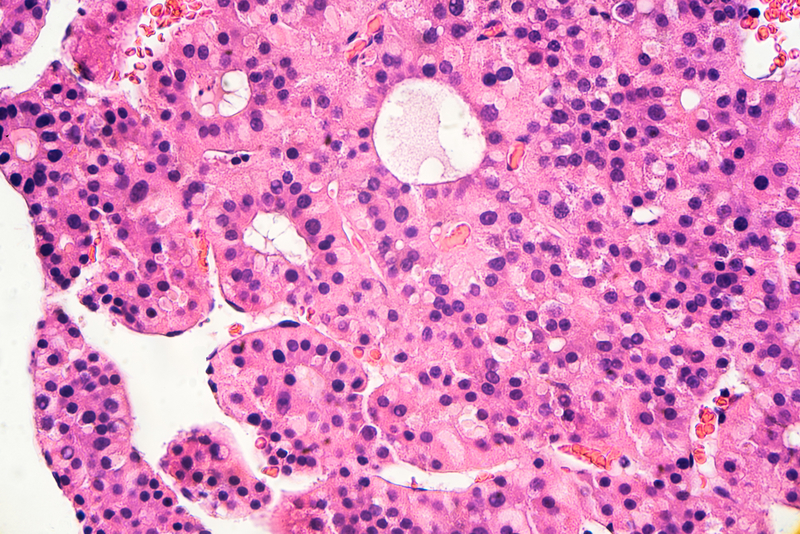

Treatment with atezolizumab combined with bevacizumab administered first-line in patients with unresectable hepatocelluar carcinoma (HCC) significantly prolonged overall survival (OS) and progression-free survival (PFS) compared to the current standard of care, sorafenib, according to findings presented at the ESMO Asia 2019 Congress (22-24 November, Singapore).

On behalf of colleagues, Prof. Ann Lii-Cheng of the National Taiwan University Cancer Center and National Taiwan University Hospital in Taipei, Taiwan presented findings from the primary analysis of data from the phase 3 IMbrave150 trial (NCT03434379) of atezolizumab plus bevacizumab vs sorafenib in patients with unresectable HCC.